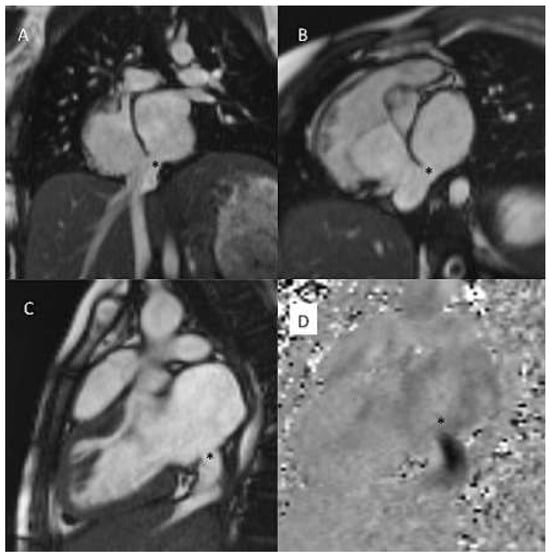

Figure 4.

(a) Late gadolinium enhancement (LGE). 21-year-old patient with arterial switch for transposition of the great arteries (TGA) after postoperative myocardial ischaemia. Extensive area with subendocardial LGE in anterolateral segment (A) and in the inferior mid-ventricular segment (B). (b) Patient with transannular patch repair and VSD closure for tetralogy of Fallot and residual severe PR. LGE in RVOT aneurysm (A), LGE of the RVOT aneurysm and VSD patch area and inferior insertion point (RV hypertrophy) (B), LGE in the RV free wall (C−D).